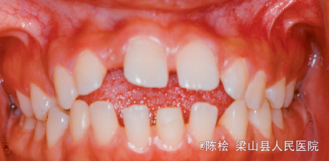

18岁女性,主诉前牙咬不到

伸舌吞咽习惯,前牙4-4开合3mm,上下牙列散隙

诊断:开合 治疗:双侧第一第二磨牙带环上制作TPA,同时弓丝伸至前牙段弯成腭刺,腭刺破除伸舌吞咽的不良习惯,TPA压低双侧后牙,降低后牙槽高度,改善开合.